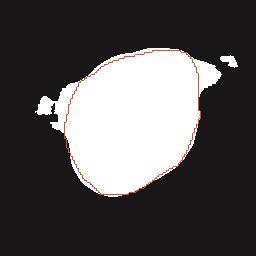

乳腺癌是全球女性最常见的恶性肿瘤之一,准确的病变分割对于乳腺癌的早期诊断与治疗具有重要意义。然而,由于病变形态的多样性以及超声成像机制的复杂性,现有基于深度学习的乳腺超声图像病变分割方法在分割准确性方面仍面临巨大挑战。为进一步提升乳腺超声图像中病变区域的分割精度,该文基于经典U-Net架构,提出了一种新型乳腺超声图像病变分割网络(CWSASKM-BBAM-Net)。首先,在网络中引入逐通道空间自适应选择核卷积模块(CWSASKM),根据不同通道的语义特征为每个空间位置自适应选择感受野大小,以增强多尺度信息的建模能力;然后,引入双向边界感知机制(BBAM),通过融合正向与反向注意力,对目标显著区域及其边界进行协同建模,同时逐步提升对非显著区域与病变区域的区分能力,以进一步强化边界信息的表达;最后,在3组公开乳腺超声图像数据集(BUSI、UDIAT和STU)上开展分割实验。结果表明:该方法在数据集BUSI上的杰卡德指数、精确率、召回率和Dice相似系数分别为71.97%、82.85%、81.40%和80.44%,较次优方法分别提升1.69、1.05、1.28和1.84个百分点;在数据集UDIAT上,这4项指标分别达到78.14%、88.31%、86.73%和86.10%,较次优方法分别提升了2.75、2.04、0.56和2.01个百分点;在外部数据集STU上,该方法也取得了优于其他方法的整体表现。实验结果表明,CWSASKM-BBAM-Net在乳腺超声图像分割任务中展现出更优的整体性能。